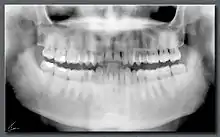

Ortopantomografía

La ortopantomografía o radiografía panorámica es una técnica radiológica que representa, en una única película, una imagen general de los maxilares, la mandíbula y los dientes. Por tanto, es de primordial utilidad en el área dentomaxilomandibular.

Su papel en el diagnóstico odontológico, no solo de los dientes sino también del maxilar y mandíbula, es fundamental. Sin la ortopantomografía el odontólogo perdería una gran ayuda en la mayoría de las especialidades de su campo. Prácticamente es utilizada de forma sistemática en odontología, llegando a ser un arma diagnóstica rutinaria. El valor diagnóstico de la ortopantomografía en cirugía bucal, implantología, ortodoncia, periodoncia y en patología oral y dental está claramente demostrado.

El término de radiografía panorámica es el más comúnmente utilizado, ya que la radiografía resultante muestra una visión panorámica de la cara y parte inferior de la cabeza. Laudenback describe la ortopantomografía como uno de los inventos radiológicos más originales de los últimos decenios. El 40% de los hallazgos patológicos principales y secundarios se descubren a partir de ella. Amplía el campo de diagnóstico en un 70% y reduce la dosis de radiación de la superficie cutánea en un 90% con respecto a las series radiográficas periapicales.